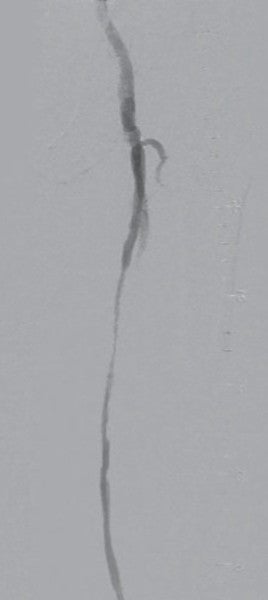

対側CFAより6 Fr 45 cm長のガイディングシースを挿入し山越えにて左EIA遠位部に進めた。この時点で圧波形は問題なかったため、手技を継続することとした。まず、5.5 Fr 100 cm長のガイディングカテーテルのバックアップ下、IVUSガイドに0.014 inchガイドワイヤー(先端荷重3 gポリマージャケットタイプ)を進めたところ、比較的容易にガイドワイヤー通過に成功した。IVUSでは全長にわたり intraplaqueを通過していたものの、血栓成分の多いプラークと考えられた。このため、5.5 FrのガイディングカテーテルをSFA遠位部に先進し、フィルターワイヤー(径 8 mm)を膝窩動脈に留置し遠位部保護を行った。続いて、5.5 Frガイディングカテーテルを用いて血栓吸引を行ったうえで、小径バルーン径 4.0 mm / 長 220 mmを使用し6 atmで前拡張した。(図3)この時点で造影にて末梢塞栓のないことを確認しフィルターワイヤーを回収、0.035 inchガイドワイヤーを用いて7 Fr 55 cm長のガイディングシースへ交換した。0.014 inchガイドワイヤー(先端荷重 1 g 親水性コートタイプ)を挿入後、SFA遠位よりバイアバーン® ステントグラフト径 7.0 mm / 長 150 mmを留置し、バルーン径 6.0 mm / 長 80 mmを用いてステントグラフト内のみ 18 atmで後拡張を行った。続いて、SFA近位部のlanding zoneをIVUSマーキングしたうえで、(図4)バイアバーン® ステントグラフト径 7.0 mm / 長 100 mmを追加留置した。先述のバルーン径 6.0 mm / 長 80 mmを用いて高圧拡張の後、近位部のみバルーン径 7.0 mm / 長 100 mmを使用し12 atmで後拡張を追加した。IVUSにてステントグラフトの拡張が良好かつmalpositionがないことを確認した。 最後に、EIAに対してベアメタルステント(BMS)径 10 mm / 長 60 mmを留置、後拡張を行って手技を終了した。(図5、6)